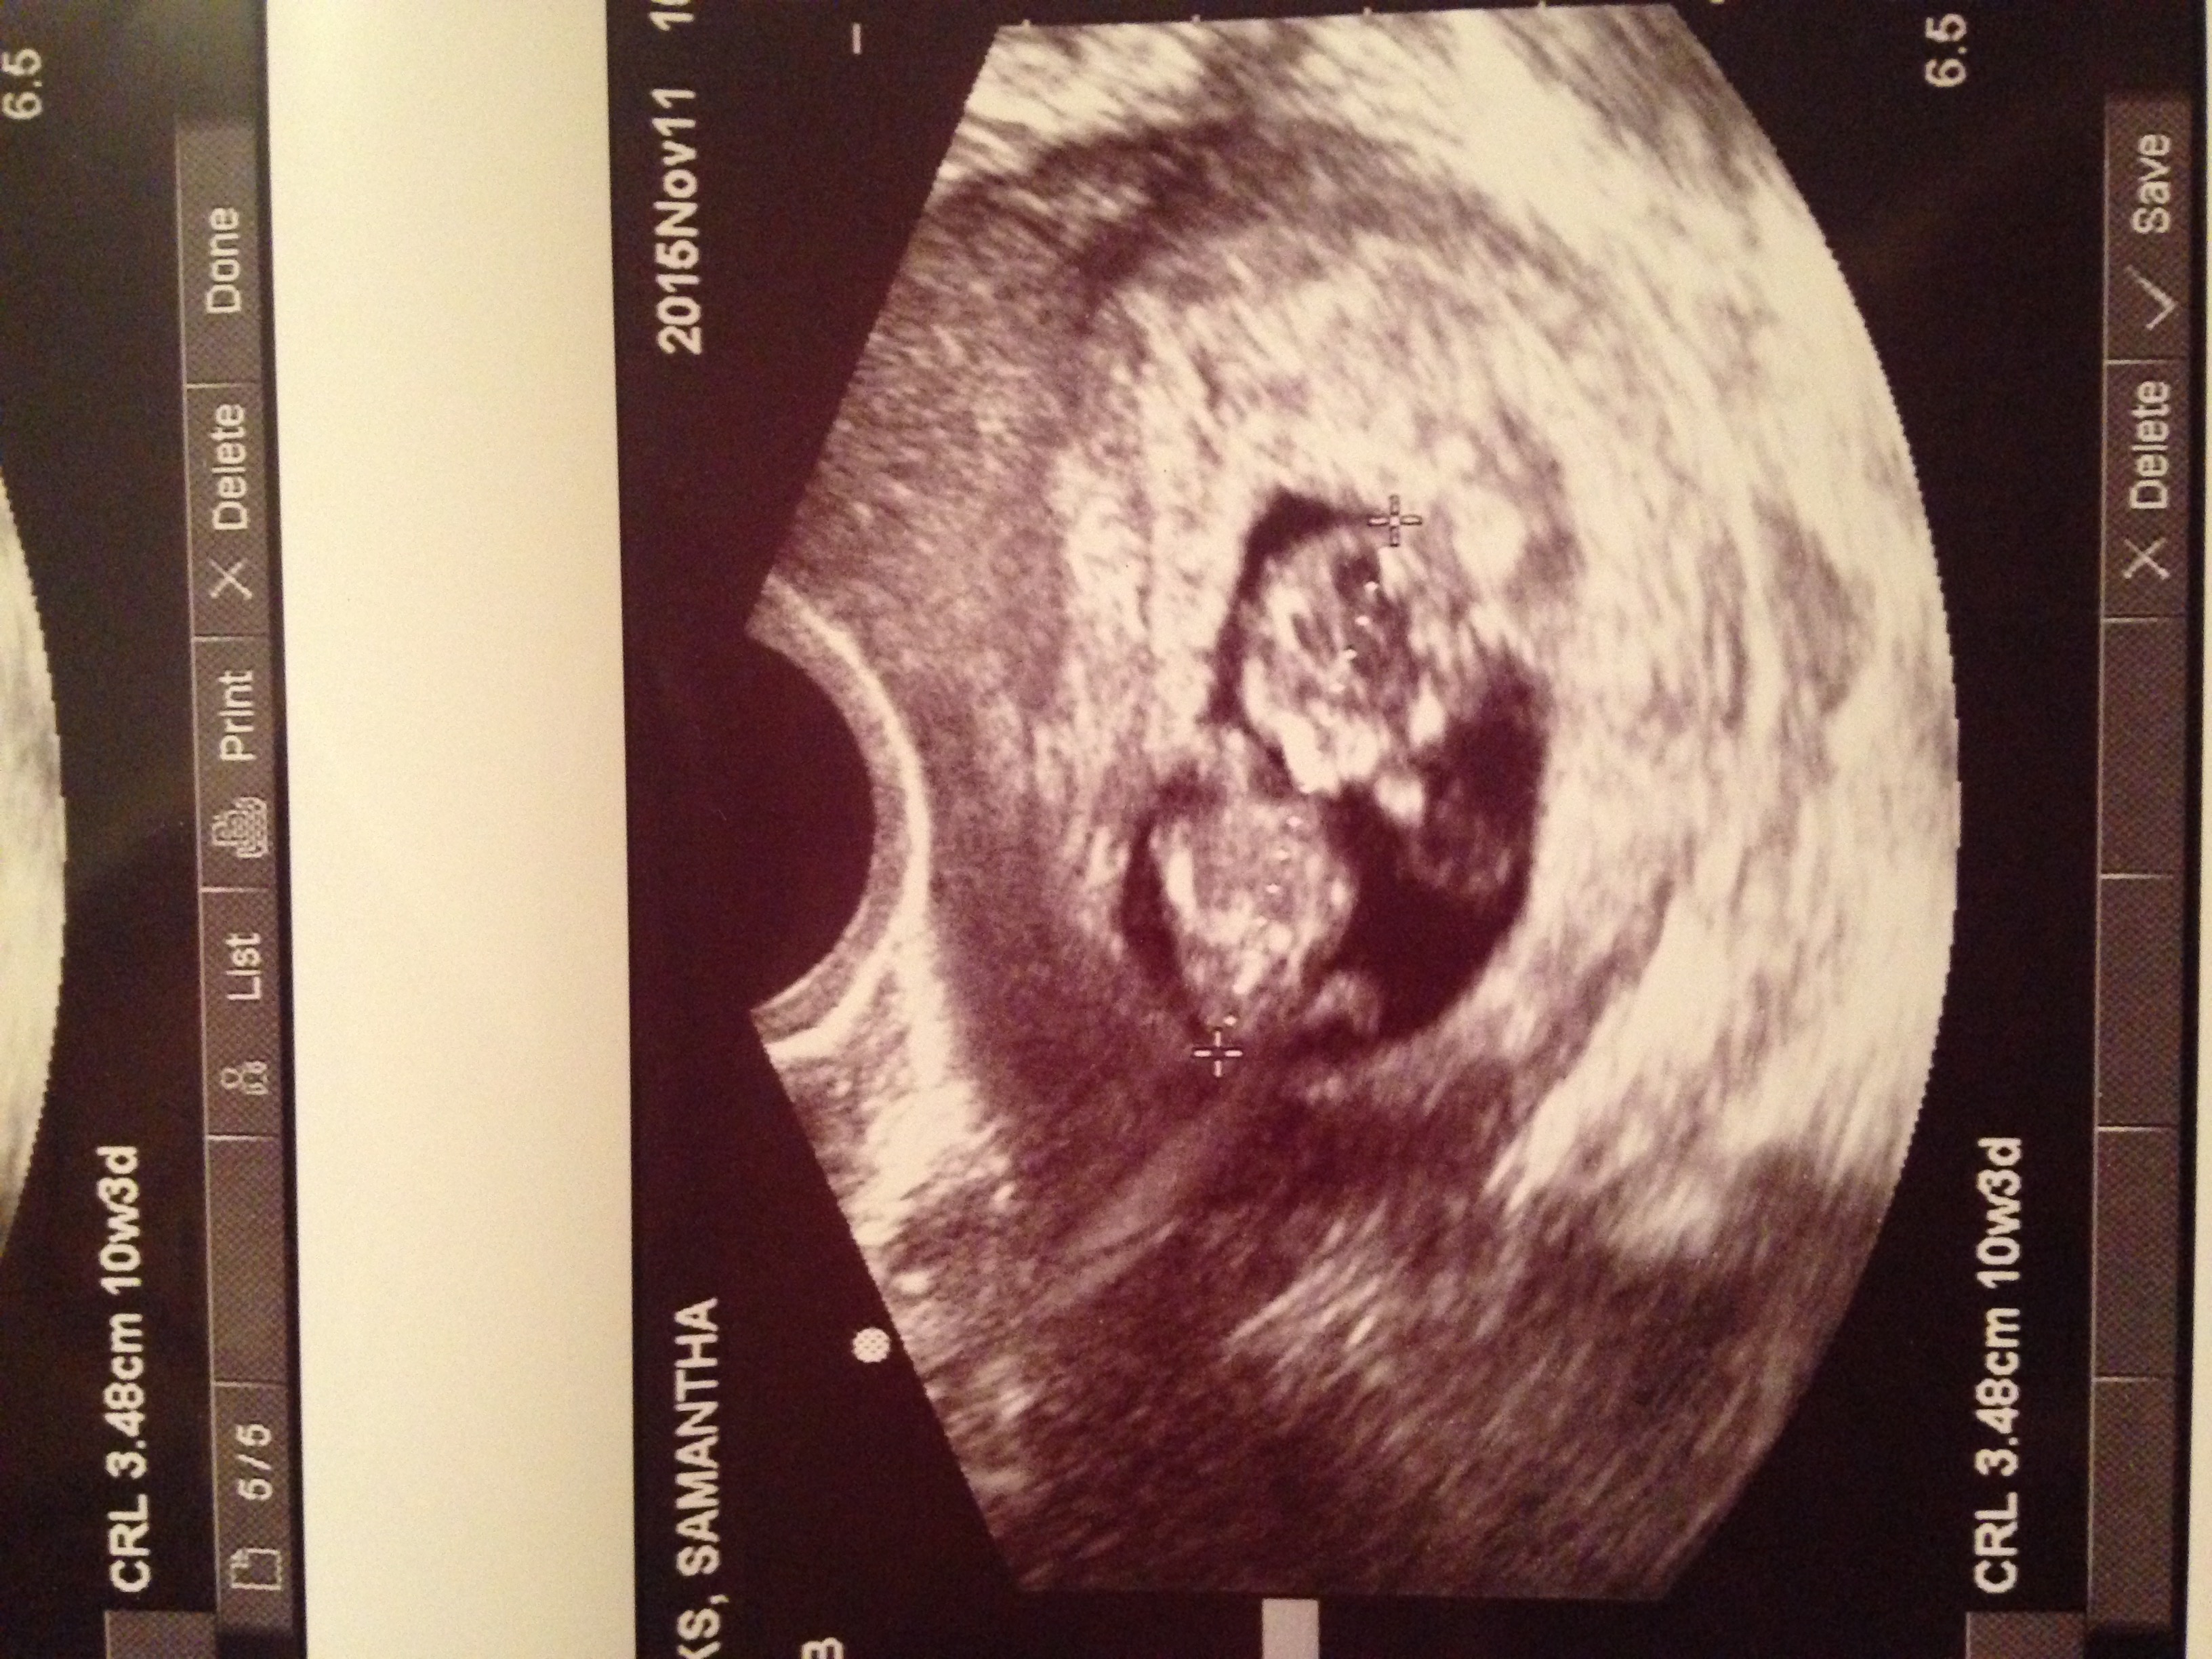

Today was my first ultrasound! I feel so relieved now that everything went well. I'm measuring as I should be. I'm 10w1d. The baby's heart beat was 163! I'm so in love! I can't stop looking at my pictures. I also got to see 3D and it was amazing. Feels so much more real now! I'll have to wait I guess to post my pic